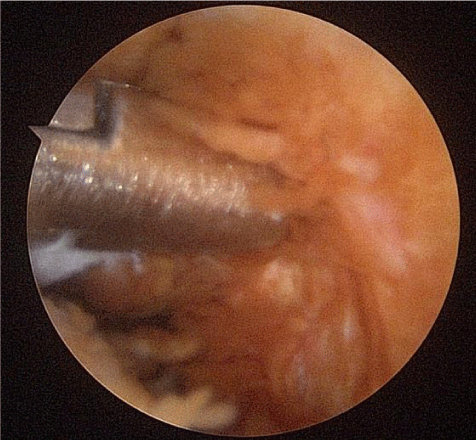

A 24-year-old female presented with a two-month history of right TMJ pain and locking. Examination revealed a 33mm mouth-opening with deviation to the right, bilateral mandibular condyles and right masseter tenderness to palpation, intact cranial nerves and no joint loading. There was no facial or preauricular swelling. The CT scan showed left greater than right condylar flattening with intact cortical outline and no osteolysis (Figure 1). The MRI showed bilaterally displaced discs with the left being deformed (Figure 2). The patient then underwent bilateral arthroscopy. Diagnostic arthroscopy on the left revealed synovial growth with striking reddish-orange discoloration. The disc was seemingly spared from the disease process (Figure 3,4). Synovectomy and debridement were completed. Histologic examination revealed PVNS (Figure 5). On her 10-month follow-up she reported significant improvement in pain and functional-limitation scores. She had a painless, symmetric 35mm mouth-opening with no joint tenderness or loading.